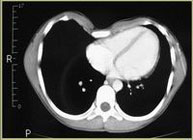

Los datos médicos del paciente, más la exploración clínica realizada por el equipo de cirugía, junto a un análisis pormenorizado de las imágenes del TAC y las reconstrucciones digitales en 3D de cada tórax realizadas conjuntamente con el equipo de ingenieros de Ventura Medical Technologies, son la base para determinar si la técnica Pectus Up está indicada y como se debe proceder en cada uno de los pacientes.

Pectus Excavatum Pectus Excavatum Asimétrico Índice de Asimetría 0.6 (+R/-L)(|AI|> 0.05 Asimétrico) Índice de Haller 4.5 (HI >3.5) Índice de Corrección 49.13% Rotación esternal 18.1 ° (a la derecha)

Informe de evaluación del TAC de un paciente enviada al cirujano